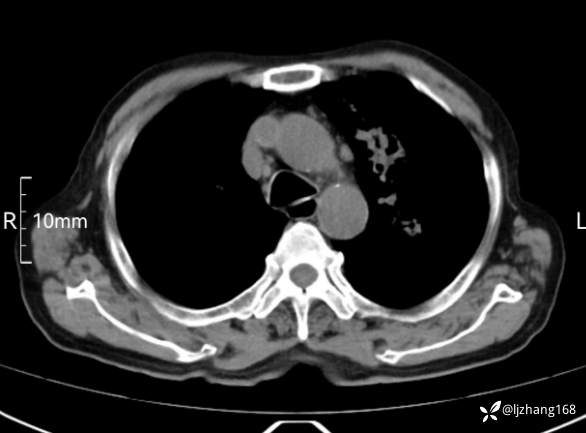

辅助检查:胸部CT:双肺肺气肿,间质性病变,血气分析:PH 7.413, PCO2 29.2mmHg, PO2,81.8mmHg,乳酸 3.3mmol/1,剩余碱-4.0mmol/1,HC03 18.8mmol/1。全血超敏C反应蛋白:超敏C反应蛋白 135.60 mg/L、 白细胞 14x19^9/L,中性粒细胞11.6x10^9/L。